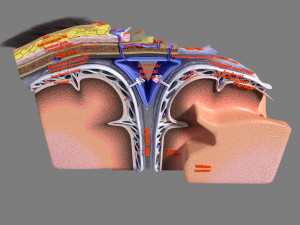

A blend model of brain along with its covering layers (meninges), skull bone and scalp labelled in detail and anatomically precise. The parts depicted are white, gray, pia, arachnoid, dura, bone, skin, fat, aponeurosis, periosteum, falx cerebri and more.

The material is high resolution image textures and normal maps based on non overlapping UVs. The texture and normal maps are packed with the blend file itself.